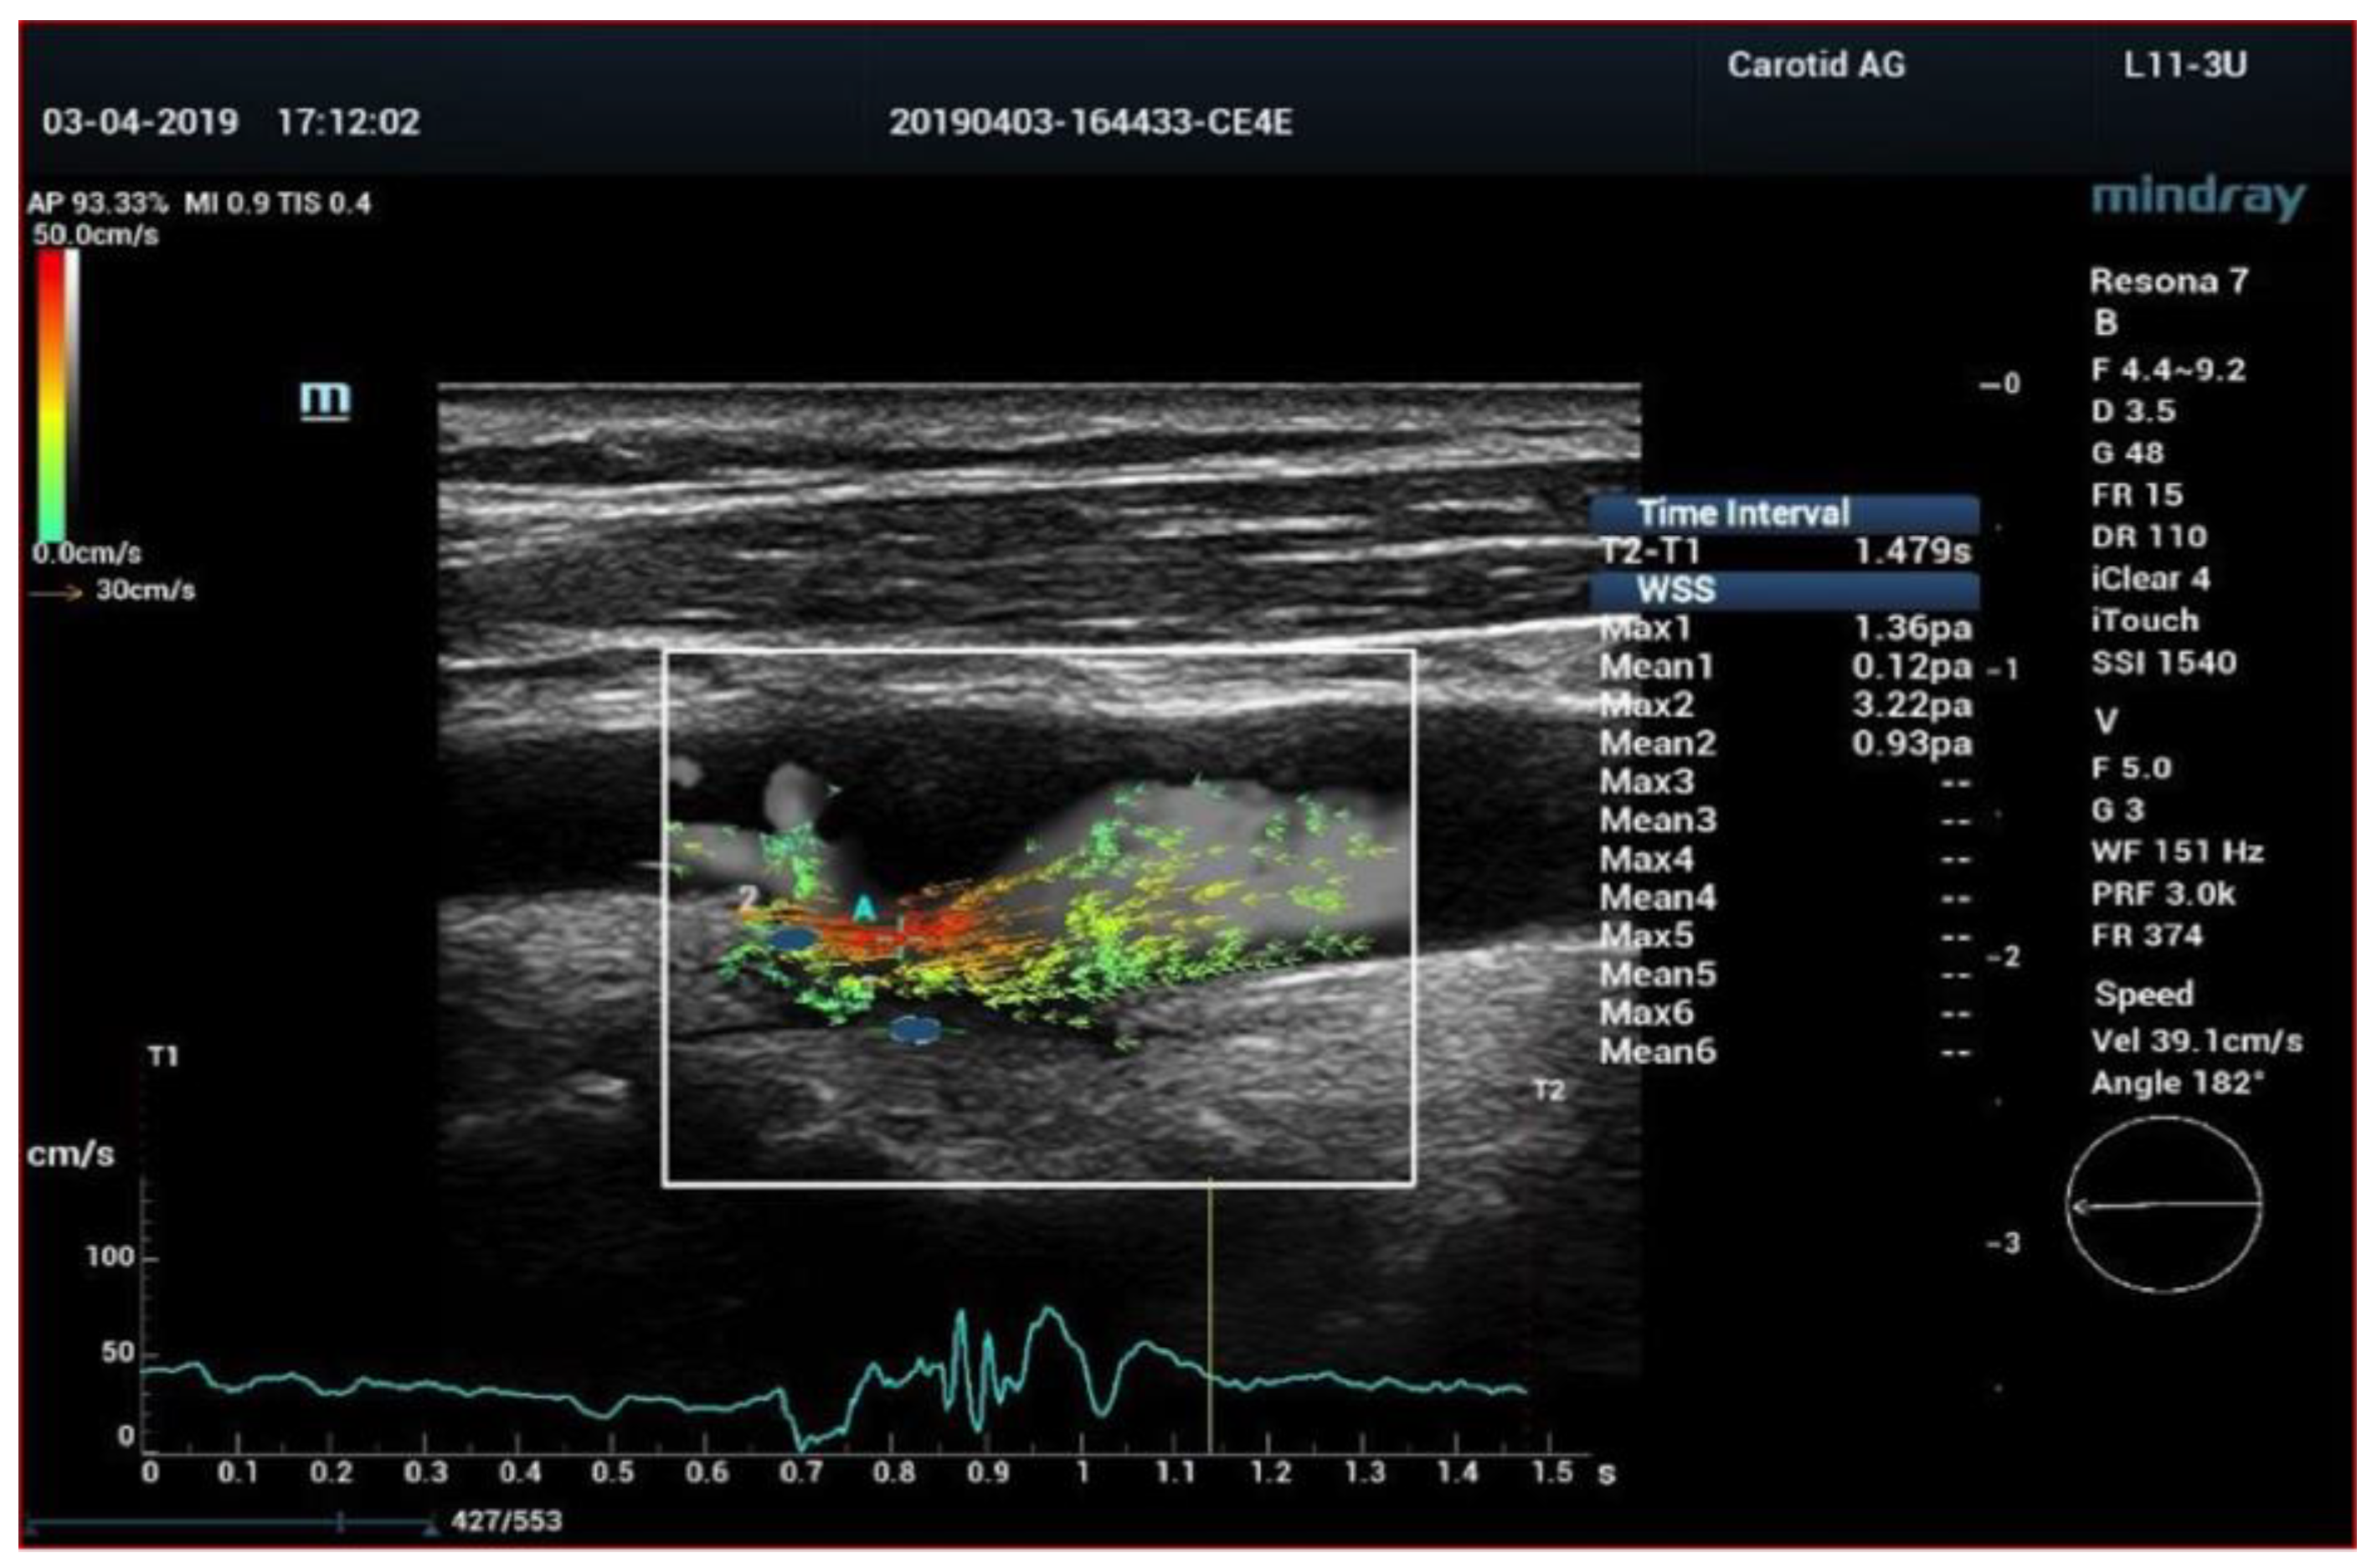

- Qiu, Y.; Dong, Y.; Mao, F.; Zhang, Q.; Yang, D.; Chen, K.; Shi, S.; Zuo, D.; Tian, X.; Yu, L.; et al. High-Frame Rate Vector Flow Imaging Technique: Initial Application in Evaluating the Hemodynamic Changes of Carotid Stenosis Caused by Atherosclerosis. Front. Cardiovasc. Med. 2021, 8, 617391. [Google Scholar] [CrossRef] [PubMed]